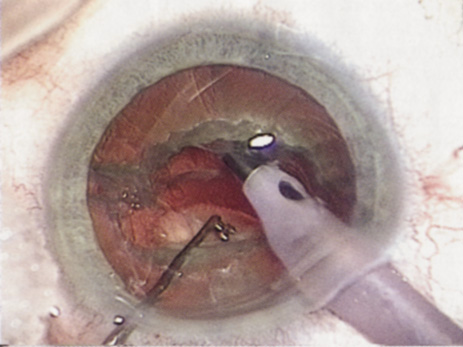

further tests guide the ophthalmologist in planning the surgery. SPECIAL MEASUREMENTS OF VISION Preoperative measurement of vision is meant to determine the patient's current state of visual function. Snellen acuity is routinely tested on all patients as part of their preoperative evaluation. This usually is performed by having the patient read a standardized chart in a darkened room. Although the Snellen acuity scale is the most ubiquitous measure of vision, it measures only one tiny aspect of visual function. Many patients may be profoundly functionally impaired by their degree of visual disability, yet may test surprisingly well measuring Snellen acuity in a darkened room. In these cases, it is incumbent on the ophthalmologist to seek to better understand and document the patient's problems by performing additional testing. Many patients are most bothered by cataract-induced glare. For these patients, acuity testing under glare situations is indicated. There are several methods to assess visual acuity reduction by glare. The choice of method is often best dictated by the patient's history. If a patient complains of glare problems in the supermarket, or other uniformly illuminated environment, the brightness acuity test can be performed (Mentor Ophthalmics). For this test, the specially illuminated handpiece is held in front of the tested eye using best spectacle correction (Fig. 1). The Snellen acuity is rechecked and can be recorded on each of three light settings. Patients who complain of glare from point sources of light, such as oncoming headlights or bright sunshine, may be best evaluated by a different form of glare testing. To simulate the environment of the patients' symptoms, Snellen acuity is measured while directing a point source of light obliquely toward the eye outside their best spectacle correction or outside of a phoropter dialed in with their best manifest refraction (Fig. 2). Still other patients' problems may center on difficulty with reading, seeing street signs, or distinguishing fine patterns. In these individuals, the complaints are related more to contrast; therefore, contrast testing is most appropriate. There are a number of ways to assess the effect of contrast on vision. Regan's sine wave gradients have been used frequently for research purposes and are available in some settings. Various commercial devices are now available to measure visual acuity in different contrast settings and each has its relative merits and detractions. The authors have found the Baylor Visual Acuity Tester (BVAT) monitor (Mentor Ophthalmics) testing of contrast to correlate well with patients' complaints and its simplicity is appealing to both patients and technical staff. In rare instances, patients' complaints may be primarily related to distinguishing colors. Although patients frequently remark about their dramatic improvement in color perception after cataract surgery, there are no convenient methods to document diminished color perception preoperatively. This underscores the importance of correlating patients' complaints with the biomicroscopic examination and the degree of nuclear color change. PROGNOSTIC TESTS Physicians often order special tests to help determine a patient's visual potential. Some of these tests are acuity specific. These can be particularly helpful in guiding patients who may have comorbid ocular conditions. Some devices have been designed to project a Snellen chart through the clearest area of the cataractous lens to assess retinal acuity potential such as the potential acuity meter. Studies also have shown a good predictive value by checking vision with a brightly illuminated near card.53 Of course, this can be performed with no additional office equipment. Various other commercial devices, including interferometry and various different pinhole and illumination device combinations, are available. These approaches are not possible for patients with mature cataracts. Some more general, nonspecific prognostic tests can be performed. If a patient is able to identify the colors of projected lights, this usually indicates that some cone-mediated macular function is present. Blue field endoscopy also may indicate some macular function. This test is performed by projecting a blue light into the eye. The patient may report seeing small round specks moving around in the vision. These specks correspond to white blood cells passing through the perifoveal capillaries. The Purkinje phenomenon is tested easily by rapidly wiggling a transilluminator directed toward the globe through the lower lid in a darkened room. If the patient reports a pattern of crooked lines or branches, then he or she is seeing the shadows cast by the retinal blood vessels, indicating that the posterior pole is attached and functioning to at least some degree. Although positive results from the test are encouraging, some patients may still have limited vision after surgery; similarly, some rare patients may test negatively on all these tests and still recover good vision. Diagnostic Studies Several diagnostic studies provide information that supplements the historical and clinical data obtained by the surgeon. This information enables proper preoperative patient consultation and surgical planning. This section outlines many preoperative tests used for cataract patients. A-SCAN BIOMETRY. Accurate axial length measurement is critical to determine the correct power of the implant lens for the desired refractive result. A-scan biometry is imperative in any patient undergoing cataract surgery. Both contact (applanation) and immersion varieties of A-scan ultrasound units are commercially available. With applanation biometry, a hand-held or slit-lamp mounted probe is gently touched to the corneal surface along the visual axis. Contact A-scans are user dependent and sometimes the authors adjust the surgeon-specific IOL A-constant depending on which ultrasonographer has performed the scan. Nonetheless, outstanding refractive outcomes have been achieved, and the authors have been satisfied with the contact applanation technique. With an immersion probe, a water bath around the eye acts as the medium to conduct sound waves. Although there is no direct contact of the probe with the globe, the water and water bath must, of course, remain in contact with the ocular surface and periorbita. Immersion scans may reduce interobserver variations but are less comfortable and less convenient for patients. A-scan biometry is particularly challenging in eyes containing an oil fill. In this instance laser biometry is still able to achieve excellent measures. LASER PARTIAL COHERENCE OPTICAL BIOMETRY. Although ultrasound requires continuous contact with media that conduct sound waves, laser light passes easily through any clear media, including air, making this a truly noncontact or “no touch” test. Furthermore, the speed of light is not appreciably different in the clear media of the eye and thus excellent, reliable measures can be achieved in eyes containing intraocular lenses, regardless of type and eyes with oil fills within the vitreous cavity. Although some calculation adjustments can be made depending on the pseudophakic status, the differences among implant material are not appreciable different from a practical clinical perspective. Currently, the only commercially available laser biometry device is the IOLMaster (Zeiss). The measurements obtained by the IOLMaster device are extremely reliable, reproducible, and seem to be relatively technician- and observer-independent.54,55This device also can measure keratometry, optical anterior chamber depth measurements, and “white-to-white” measurements in an automated fashion. Because it relies on the passage of laser light through the ocular media, this instrument is unable to obtain measurements in cases where the media prevent laser light passage; for example, white cataracts, axial posterior subcapsular cataracts, or corneal scarring. B-SCAN ULTRASOUND. A mature cataract precludes visualization of the fundus. A B-scan ultrasonographic examination provides a real-time, two-dimensional (2D), cross-sectional image of the globe along the marked axis of the probe (Fig. 3). Cataracts are more common in patients with chronic retinal detachment, prior trauma, or intraocular tumors; therefore, a B-scan study is helpful in excluding structural posterior segment pathology before surgery on a mature cataract. Although a negative result to B-scan evaluation is reassuring, the surgeon should remember that it does not predict postoperative visual outcome. The B-scan can be thought of as a picture of Cincinnati from an airplane; the office buildings may all be standing, but you cannot tell whether the people in them are working.